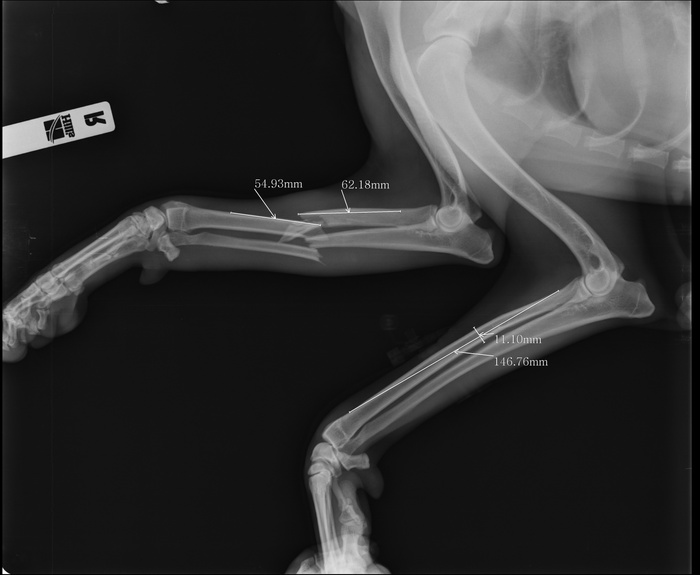

Щенок сломал лапу

Щенок сломал лапу 139 фотографий